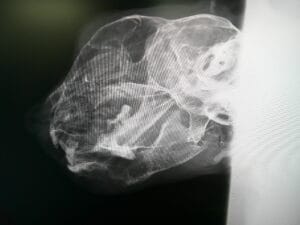

犬猫の下顎結合離開について|症例をもとに外科整復を解説下顎結合離開

下顎結合離開とは、左右の下あごをつなぐ部分が外傷で離れてしまう状態です。今回の症例では事故による離開から整復手術、術後の回復までの流れを紹介します。